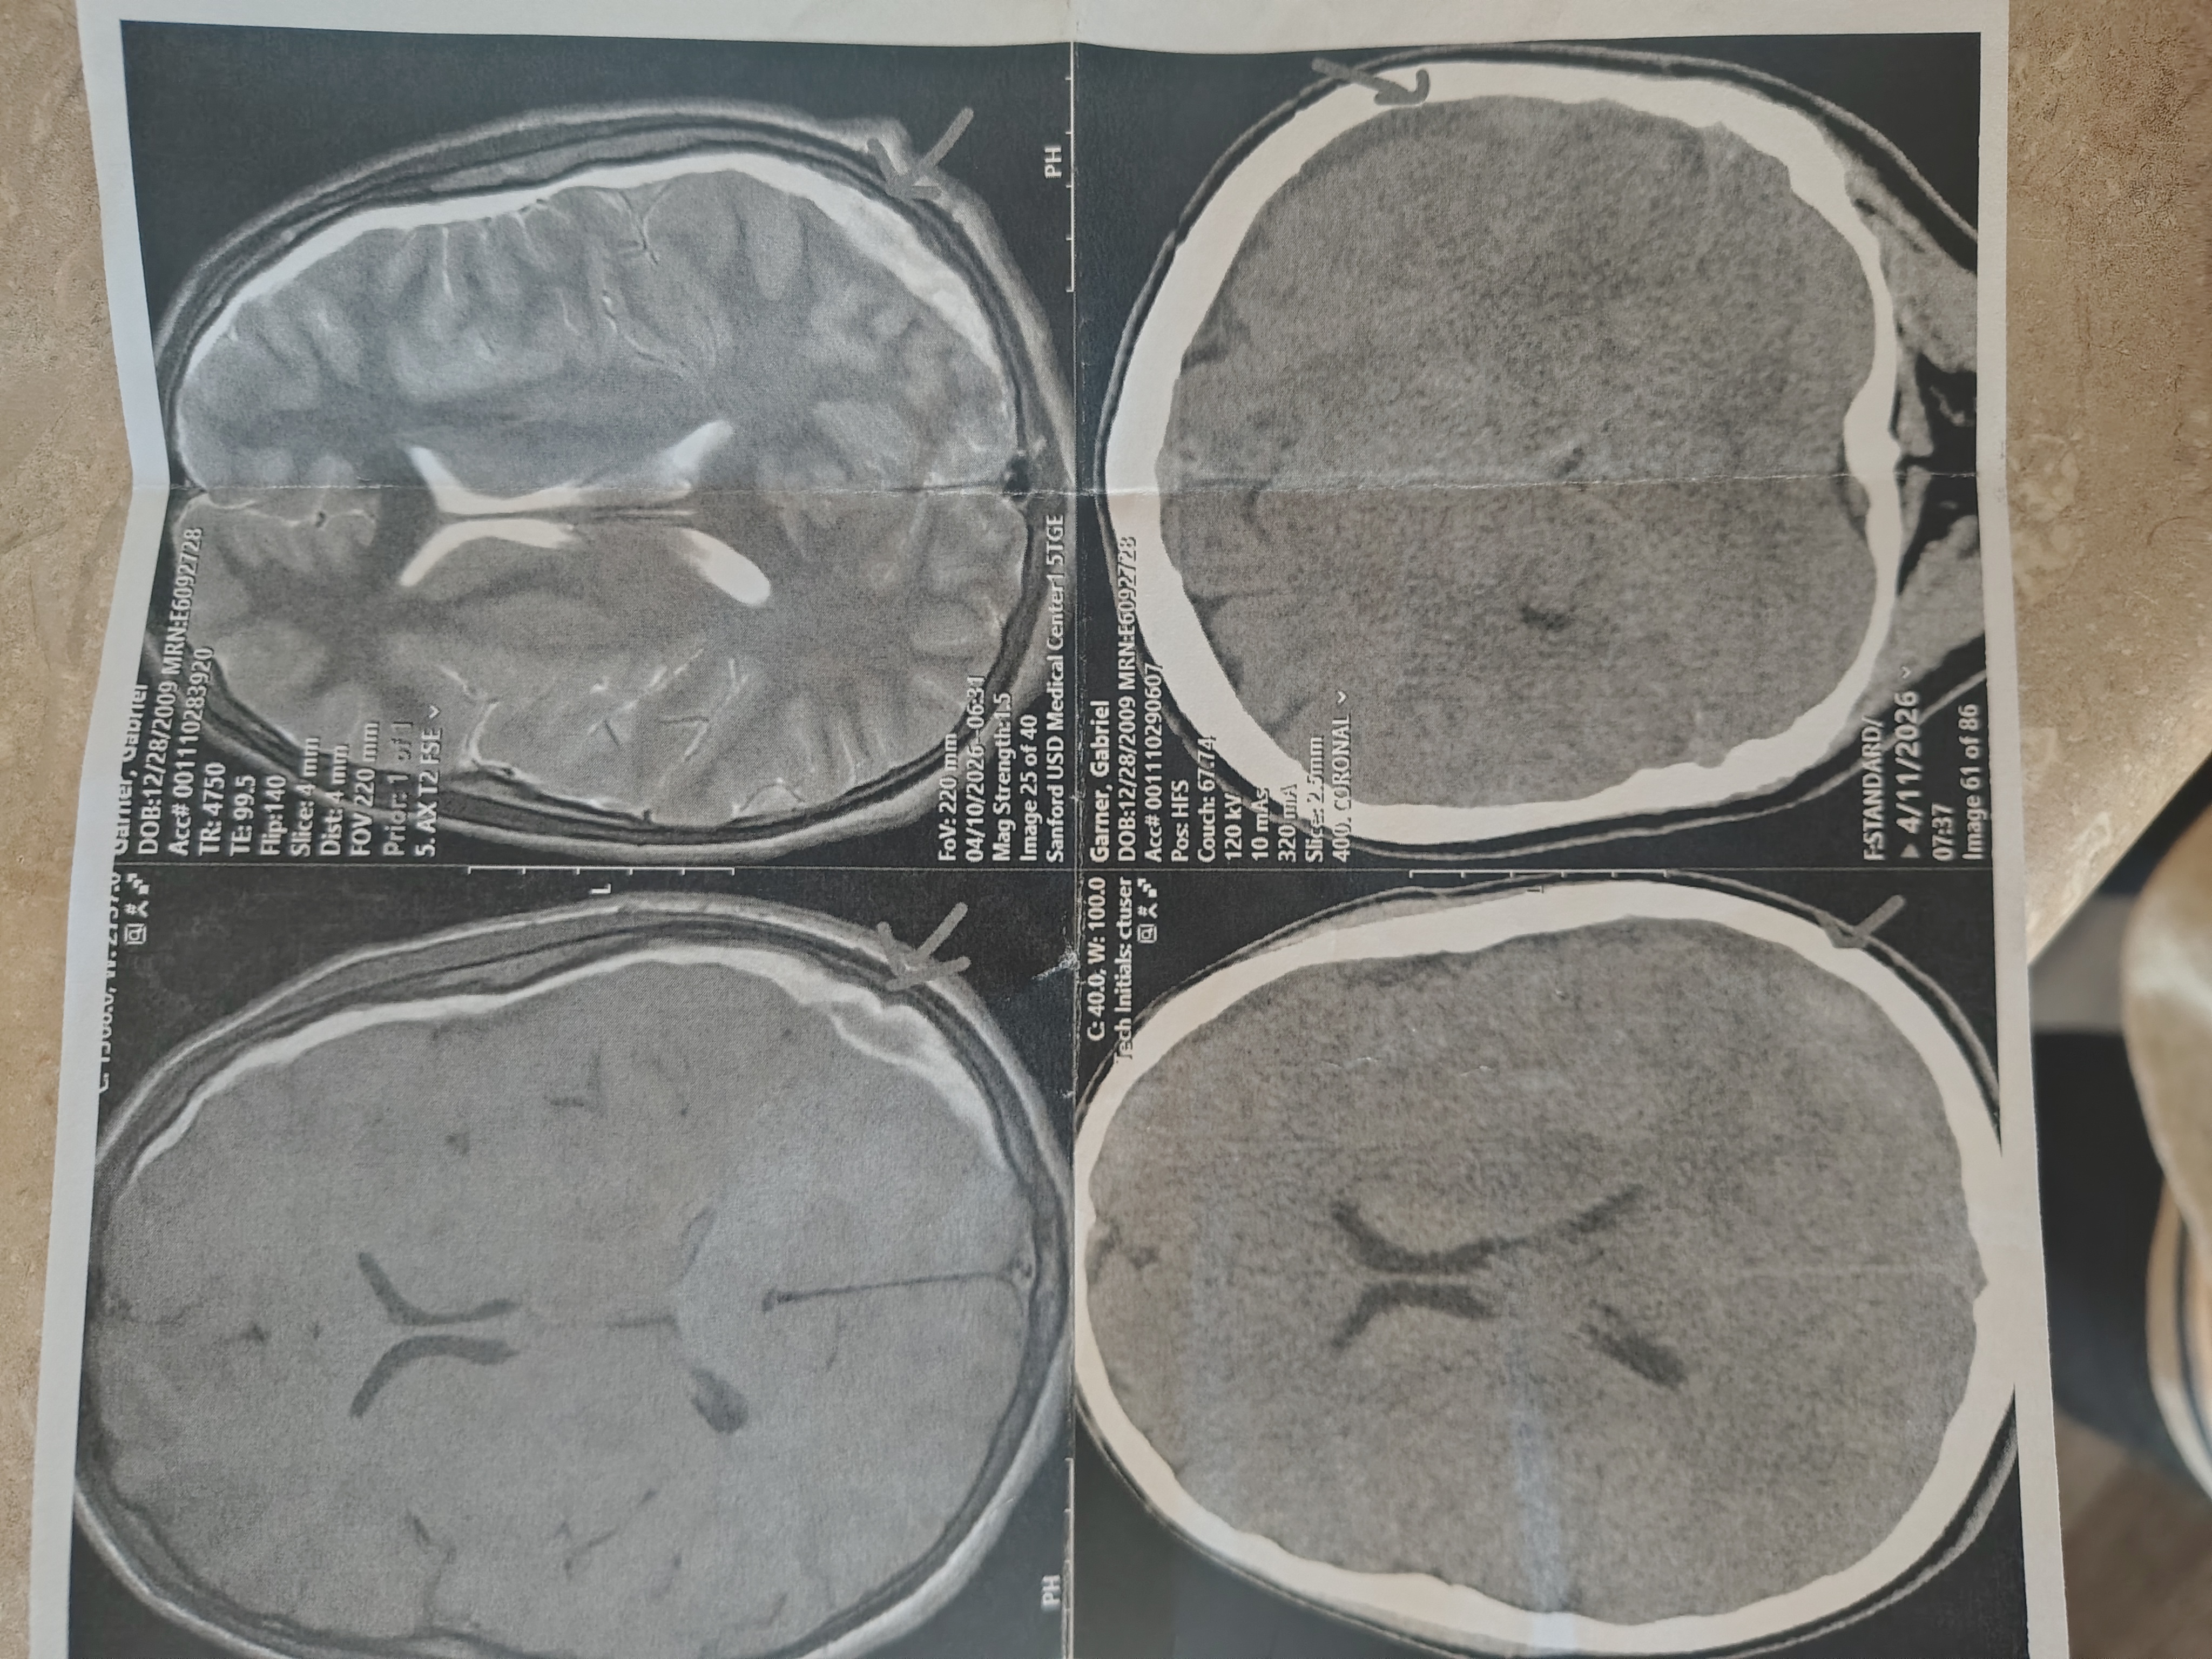

My son Noah has always been a fighter. He was born with Marfan Syndrome, a genetic condition that has brought many medical challenges into his life. Recently, we received the devastating news that Noah has developed five brain bleeds. This has turned our world upside down and required me to become his full-time caretaker, forcing me to step away from work to be by his side every day.